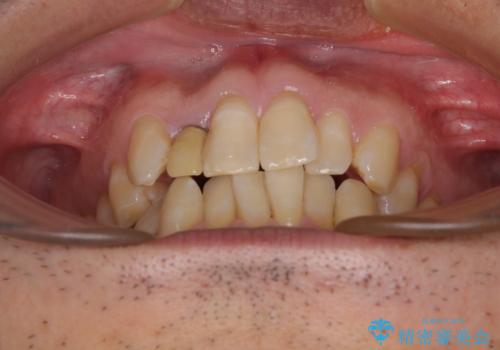

- 前歯のデコボコを気にして来院された患者様です。

目立たない装置で手軽に治したいとのことで、インビザラインにて矯正治療を行うこととしました。

前歯のクラウンは変色が著しいため、矯正治療後にオールセラミッククラウンにて補綴治療を行うこととしました。

担当医としてはもう少し前歯のデコボコを改善したいところでしたが、患者様としては十分に満足いく歯列であり、マウスピース矯正に飽きてしまったとのことで、治療終了となりました。